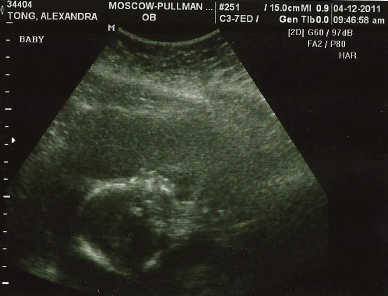

It’s my birthday today (the big 25!), and on the eve of my birthday I got a birthday present. I got to look at my cute little baby for an hour!

Speaking of doubling in size… apparently my baby is huge. He is measuring 2 weeks above his gestational age. The ultrasound tech told me that babies his age are typically around the 13-14 ounce mark, where mine was measuring nearly a pound and a half! She said if he keeps growing at this rate we might end up with a 12-13 pounder. Eek. Although, I have heard of that happening to several people and by the time 40 weeks rolls around they are average 7-8 pound babies, so I am trying not to freak out about having a giant baby! (But Paul’s mom has mentioned a few times that Tongs apparently just have big babies…) But also in good news, he’s perfectly healthy and it took a long time to get a good picture of him because he was super active! The tech said she hasn’t ever seen a baby quite as active as Togglebuttons, at least not this early in the pregnancy. He was dancing and squirming around in there so much that it was making me laugh, which in turn made him dance around all the more!